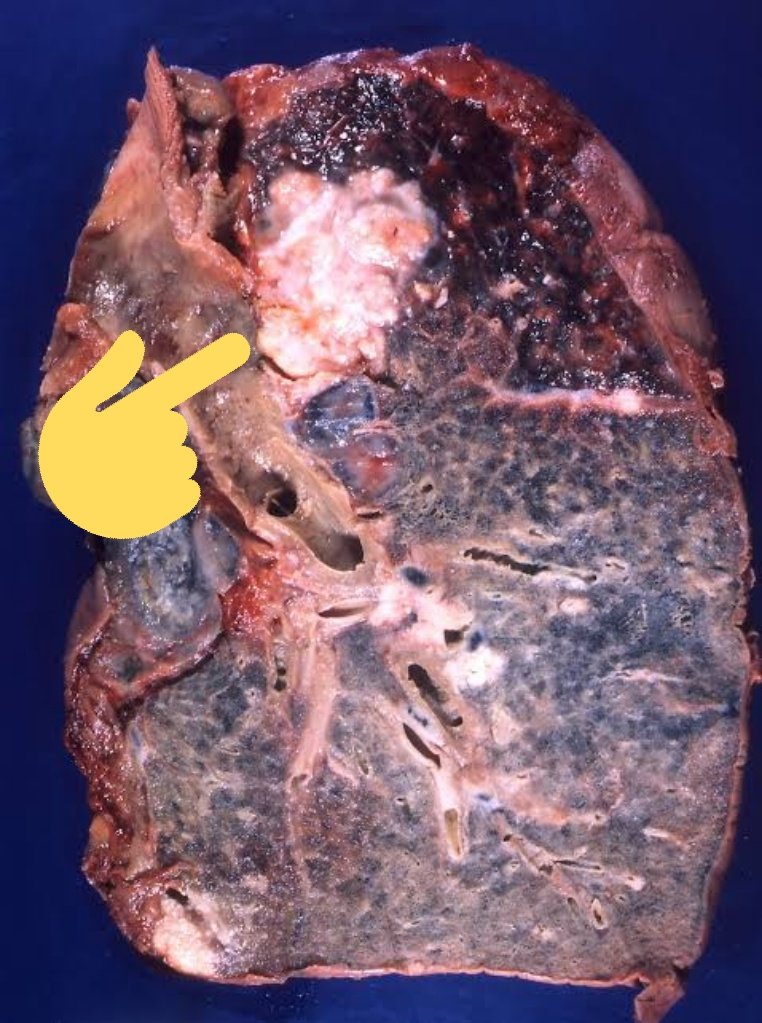

Kanker paru adalah salah satu penyebab utama kematian akibat kanker. Faktor risiko utamanya adalah kebiasaan merokok dan polusi udara.

Kanker paru adalah salah satu penyebab utama kematian akibat kanker.

Faktor risiko utamanya adalah kebiasaan merokok dan polusi udara.